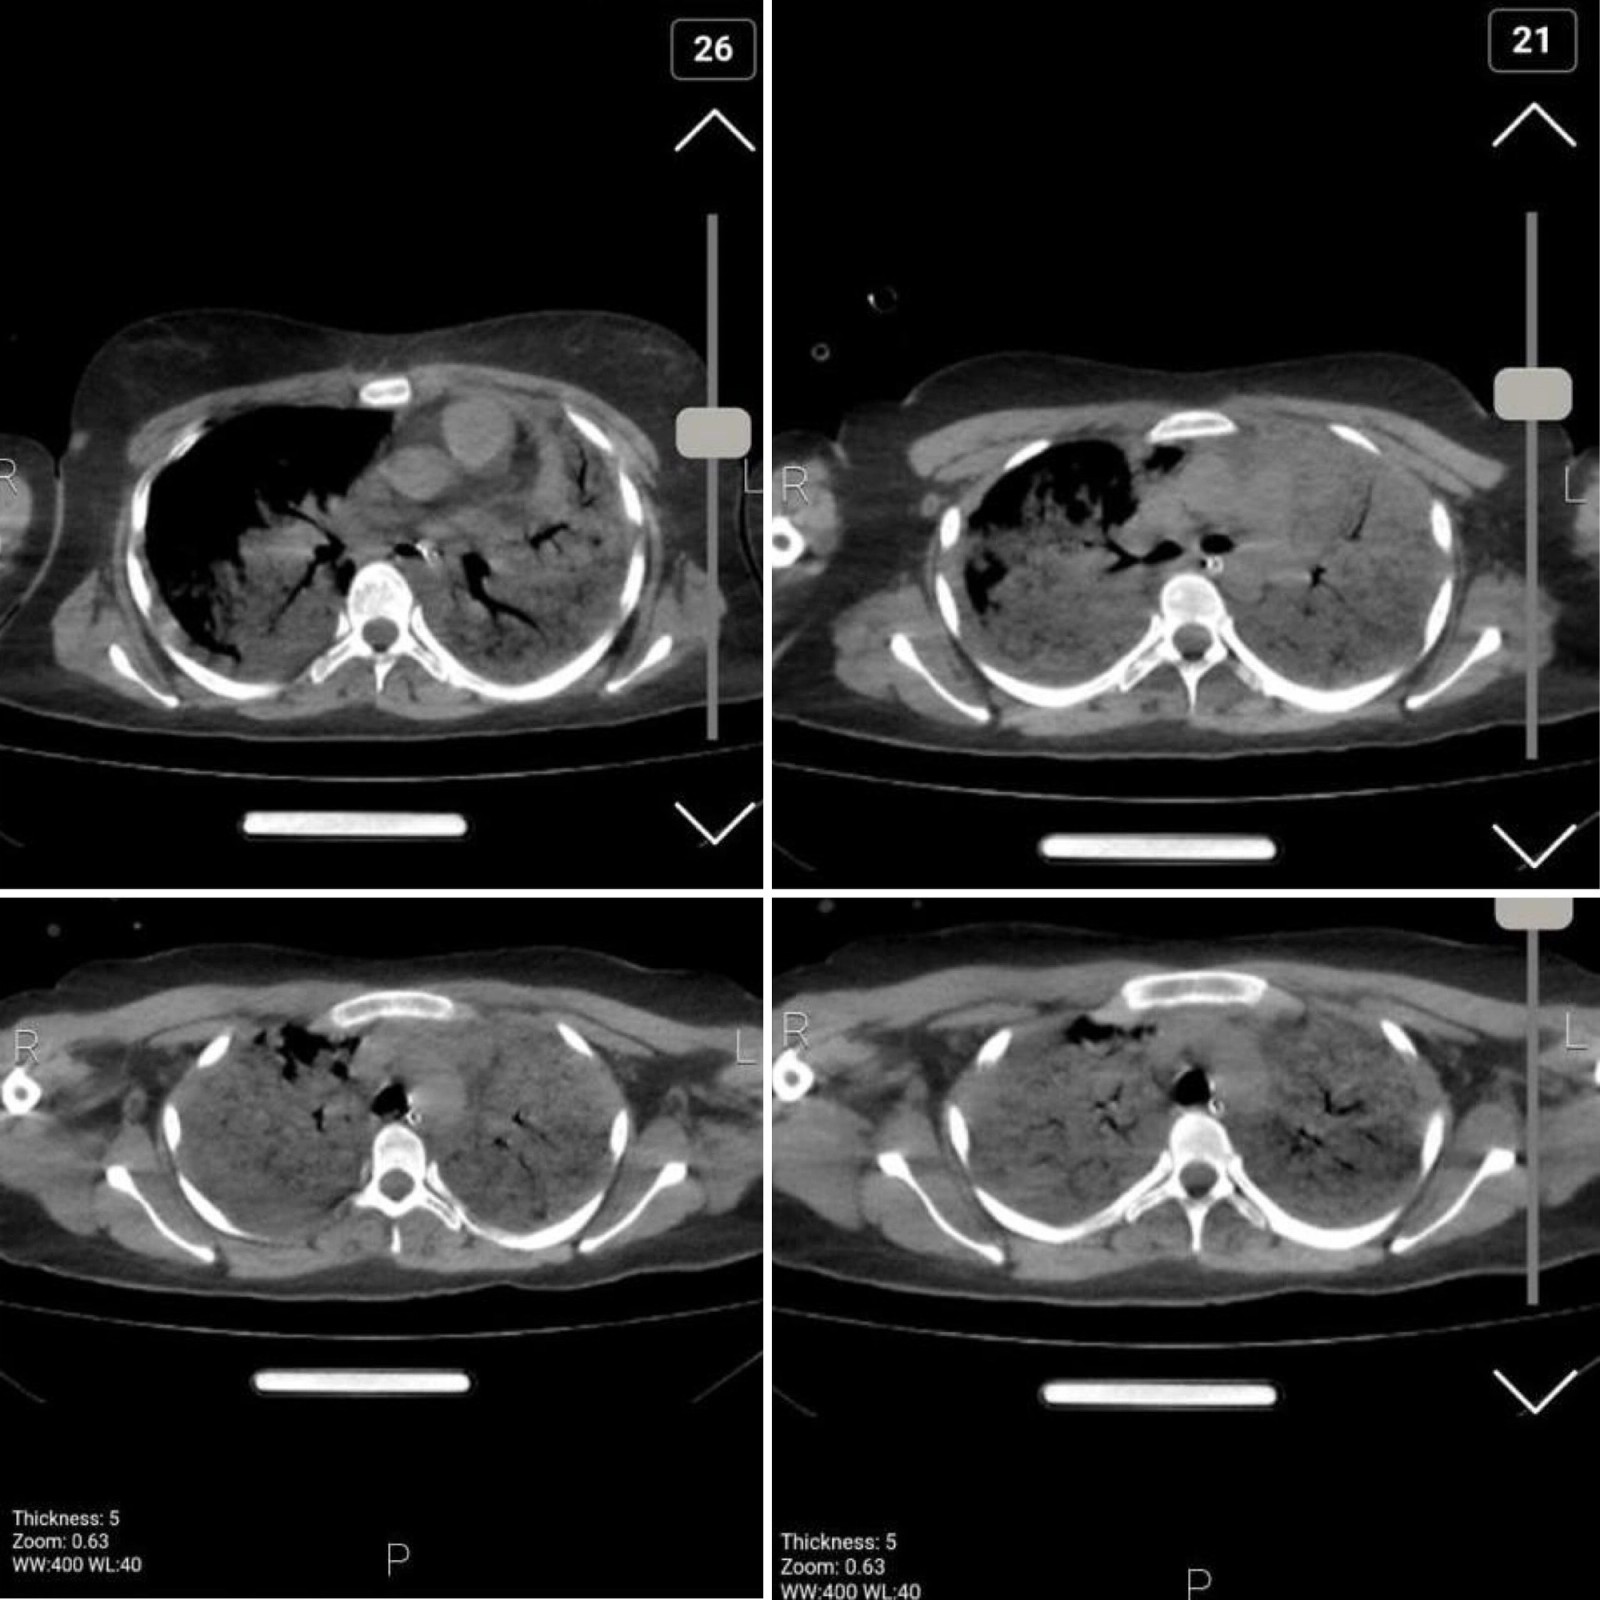

Images of her chest show bilateral diffuse alveolar hemorrhage and damage due to aspiration pneumonia, secretion retention and superimposed infection. Doctors say the results are compatible with acute respiratory distress syndrome due to brain trauma.

The source added that her lungs were filled with blood when she was transferred to the hospital and it was clear that she “could not be revived."